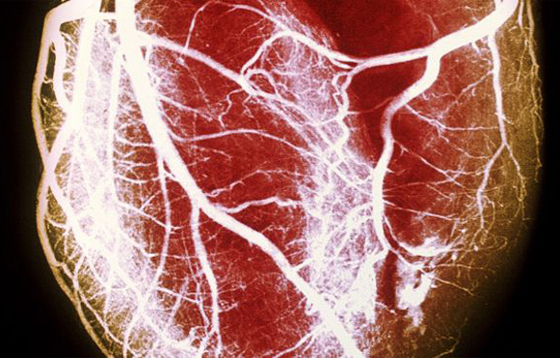

الصورة للتوضيح فقط